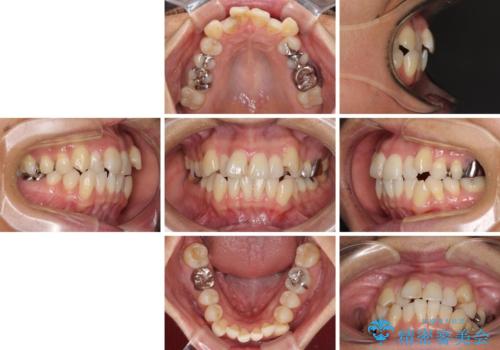

八重歯で口元が膨れている ワイヤー装置での抜歯矯正

- 八重歯と、それによる口元の膨らみを気にして来院された患者様です。

八重歯・デコボコの解消とともに、前方に張り出した上顎前歯を引っ込めることを目的とし、上下左右の第一小臼歯4歯を抜歯をしてワイヤー矯正により治療することとしました。